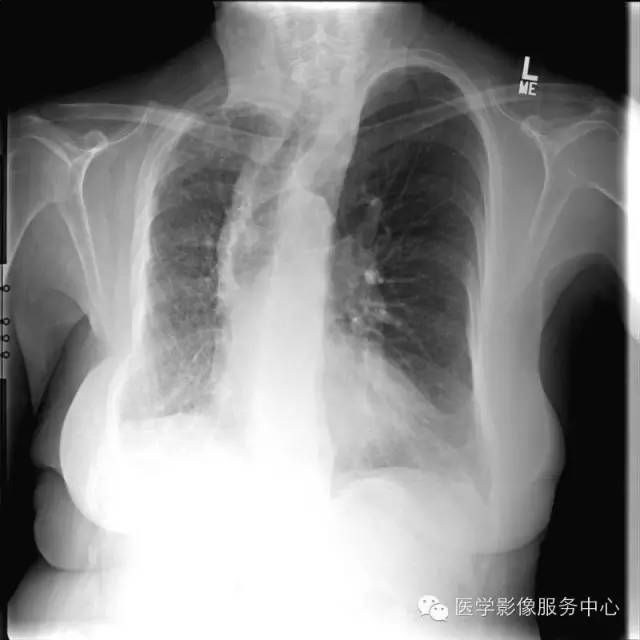

数年前胸片↑↑

UAPA典型X线表现为患侧肺纹理稀疏肺、容积减小和透光度减低;患侧肺动脉段缺如对诊断UAPA具有重要提示意义,但由于肺纹理稀疏如诊断经验不足多不能明确此征象。胸部X线平片提示病变后,应首选胸部CT平扫进一步检查。